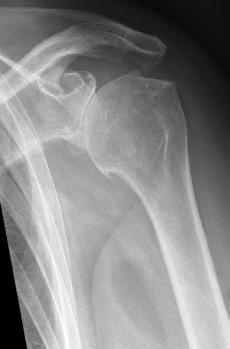

Noin joka kuudennella yli 40-vuotiaalla on todettu olevan olkapäässä nivelrikkomuutoksia, mutta monella ne eivät aiheuta oireita. Röntgenkuvassa olkapään nivelrikossa nähdään nivelraon kaventumista sekä osteofyyttejä eli luupiikkejä (kuva 1). Jos tällaisessa tilanteessa olkapäässä on liikekipua ja/ tai yösärkyä ja/tai nivelen jäykkyyttä, niin puhutaan oireisesta olkapään ni-

velrikosta. Toisen tyyppinen olkapään kulumasairaus on kiertäjäkalvosinartropatia. Oireet ovat saman tyyppisiä kuin nivelrikossa, mutta röntgenkuvassa olkaluun yläosa on noussut ylös suhteessa lapaluun maljaan (kuva 2).

Kuva 1. Tavallinen olkapään kuluma